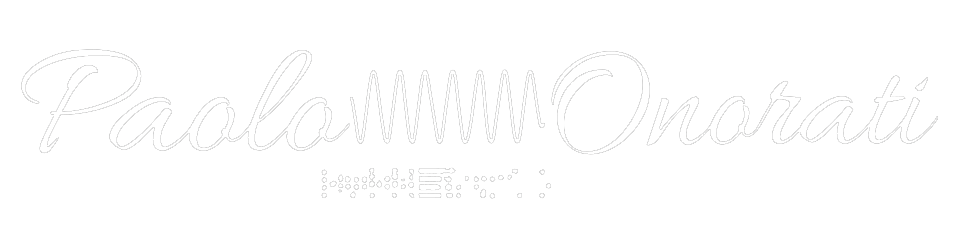

Applicazione degli Elettrodi EEG su Paziente (HD)

La procedura di applicazione degli elettrodi EEG su paziente evidenzia l’importanza della preparazione della cute, del corretto posizionamento e della gestione delle impedenze per ottenere un tracciato affidabile.